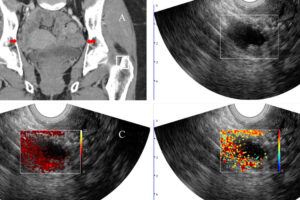

Photoacoustic imaging improves diagnostic accuracy of cancerous ovarian lesions (Links to an external site)

Quing Zhu, working with Matthew Powell, MD, and Cary Siegel, MD, from the School of Medicine, developed a new imaging method to better diagnose lesions in the ovaries and adjacent adnexa that may help to avoid unnecessary surgeries. This image shows a woman with pelvic mass and BRCA1 mutation. The arrows point to the right […]